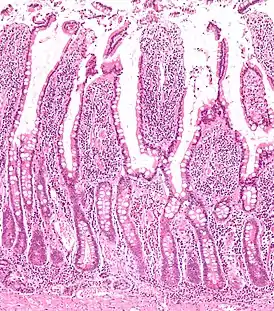

![]() Микропрепарат стенки тонкой кишки | |

Слизистая оболочка тонкой кишки характеризуется характерным рельефом, образуемым наличием целого ряда анатомических образований: циркулярных складок, ворсинок и кишечных желез или крипт. Благодаря этим структурам увеличивается общая, в том числе и всасывающая поверхность, что способствует выполнению основных биологических функций тонким отделом кишечника[5]:

- циркулярные складки (лат. plicae circulares) сформированы слизистой оболочкой и подслизистой основой тонкой кишки;

- кишечные ворсинки (лат. villi intestinales) образованы выпячиваниями слизистой оболочки пальцевидной либо листовидной формы, свободно выступающие в просвет тонкой кишки. Число ворсинок в тонкой кишке весьма значительно: наибольшее их количество в двенадцатиперстной и тощей кишках — насчитывается от 22 до 40 ворсинок на один квадратный миллиметр слизистой оболочки. Несколько меньше их в подвздошной кишке — от 18 до 31 ворсинки на один квадратный миллиметр;

- кишечные железы или крипты (лат. glandulae seu cryptae intestinales) представлены трубчатыми углублениями, расположенными в собственной пластинке слизистой оболочки, а их устья открываются в просвет тонкой кишки между кишечными ворсинками. При этом на один квадратный миллиметр поверхности слизистой оболочки тонкой кишки приходится до 100 крипт, общее их количество превышает 150 миллионов кишечных желёз на всём протяжении, а общая площадь крипт в тонкой кишке достигает 14 м2.

Стенка тонкой кишки образована серозным слоем, мышечным, состоящим из наружных продольных волокон и внутренних поперечных; и слизистой оболочки, соединяющейся посредством рыхлого подслизистого слоя с мышечным. Для слизистой оболочки тонкой кишки характерны особые поперечные складки (лат. valvulae conviventes Kerckringii), которых, однако, нет в верхней части двенадцатиперстной и в нижней части тонкой. Эти складки более часты в верхней части кишки, и каждая тянется приблизительно на половину окружности кишки. В нисходящей части двенадцатиперстной кишки имеется продольная складка на задней стенке. На нижней части этой складки на плоском сосочке открываются протоки поджелудочной железы и печени. Слизистая оболочка тонкой кишки имеет бархатистую поверхность, так как покрыта густо сидящими ворсинками (лат. villi intestinales). В стенке тонкой кишки залегают Либеркюновы железы (лат. glandulae Lieberkuehnianae), открывающиеся па́рами между ворсинками на всём протяжении тонкой кишки. В двенадцатиперстной кишке находится Бруннеровы железы, особенно многочисленные в её верхней части. По всей кишке разбросаны одиночные лимфатические узлы и скопления их — Пейеровы бляшки, наиболее многочисленные в нижнем отделе тонкой кишки. Внутри ворсинки находится сеть кровеносных капилляров и один или несколько лимфатических сосудов. Эпителий тонкой кишки цилиндрический и содержит бокаловидные клетки.